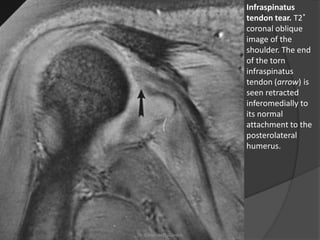

Infraspinatus

tendon tear. T2*

coronal oblique

image of the

shoulder. The end

of the torn

tendon (arrow) is

seen retracted

inferomedially to

its normal

attachment to the

posterolateral

humerus.